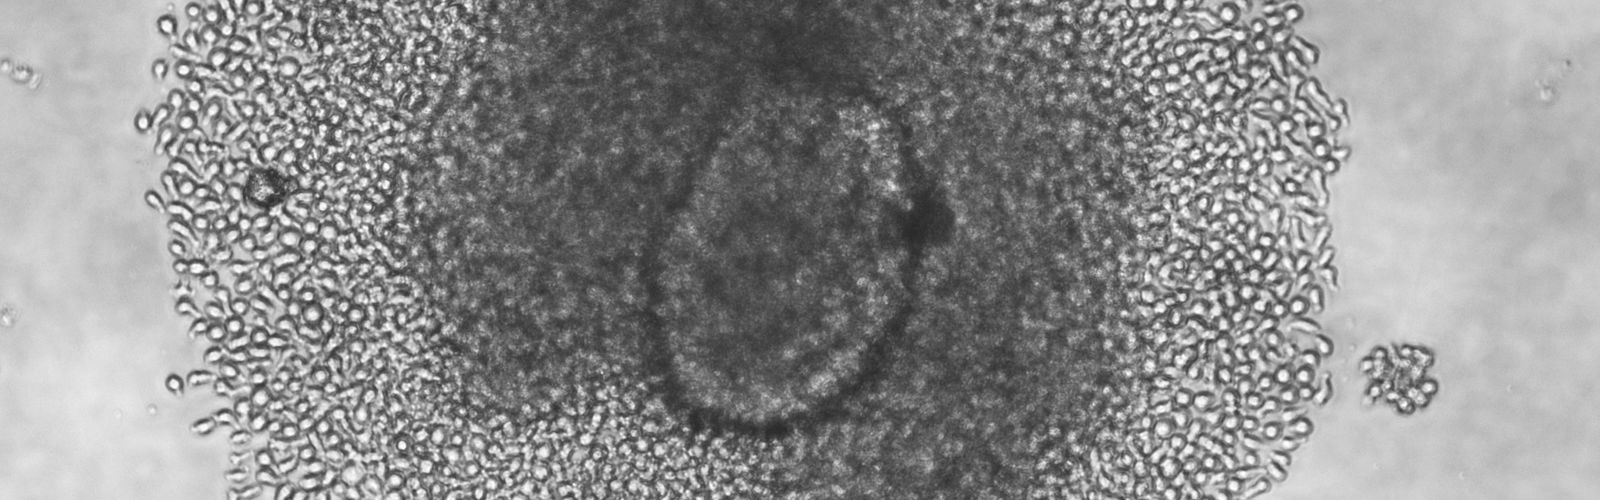

Kent Lab isolates immune cells from the islets of donors with T1D

In a highly collaborative effort, scientists at UMass Chan Medical School have isolated and characterized a large bank of live islet-infiltrating T cells directly from the islets of tissue donors with type 1 diabetes. The findings, published in Nature Medicine, have direct implications for the design of therapies and preventative strategies for those with type 1 diabetes and those at risk for developing it.

Using live islets from nine type 1 diabetic donors, Kent Lab sorted live lymphocytes by fluorescence activated cell sorting. They also used an improved tissue culture method they developed to grow lymphocytes from the islets. 236 T cell lines were derived from the islets, and they analyzed the function of 50 lines, discovering the specific reactivities of 18 lines. LEARN MORE